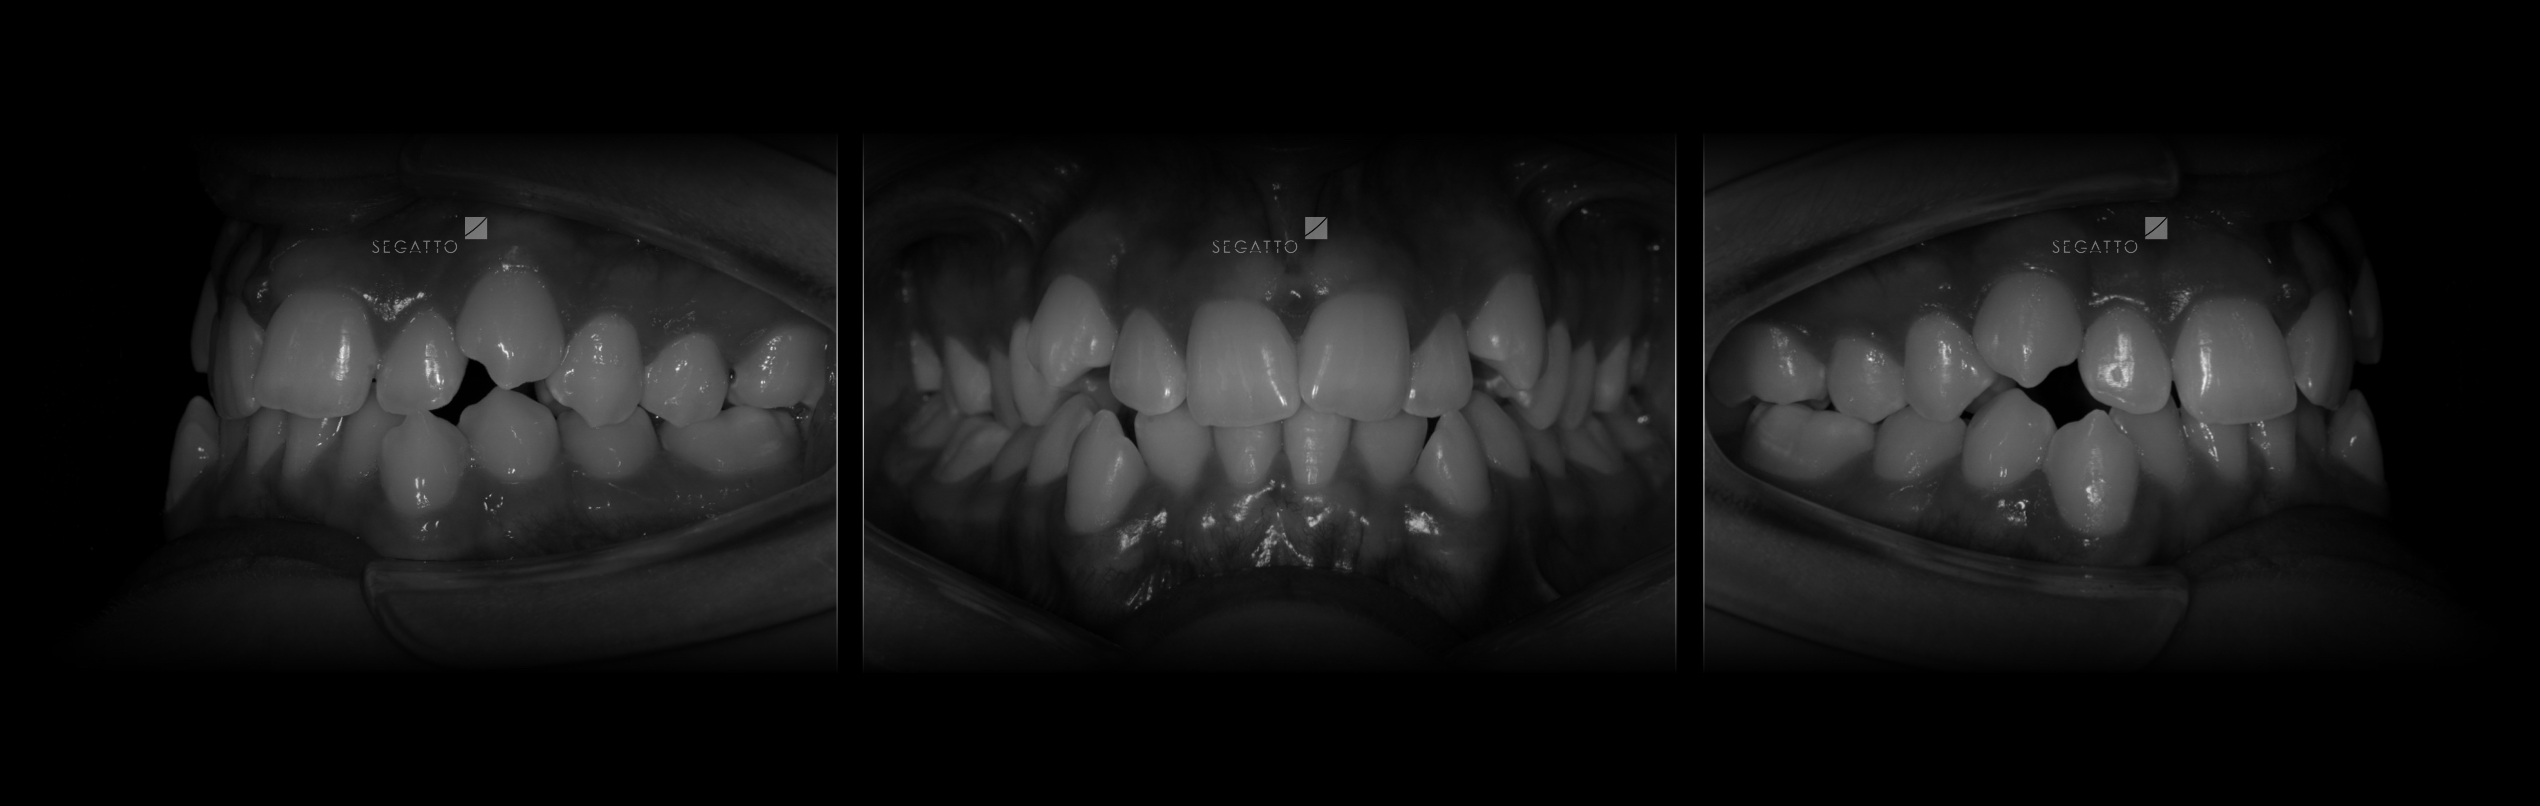

Orthodontics

Cases